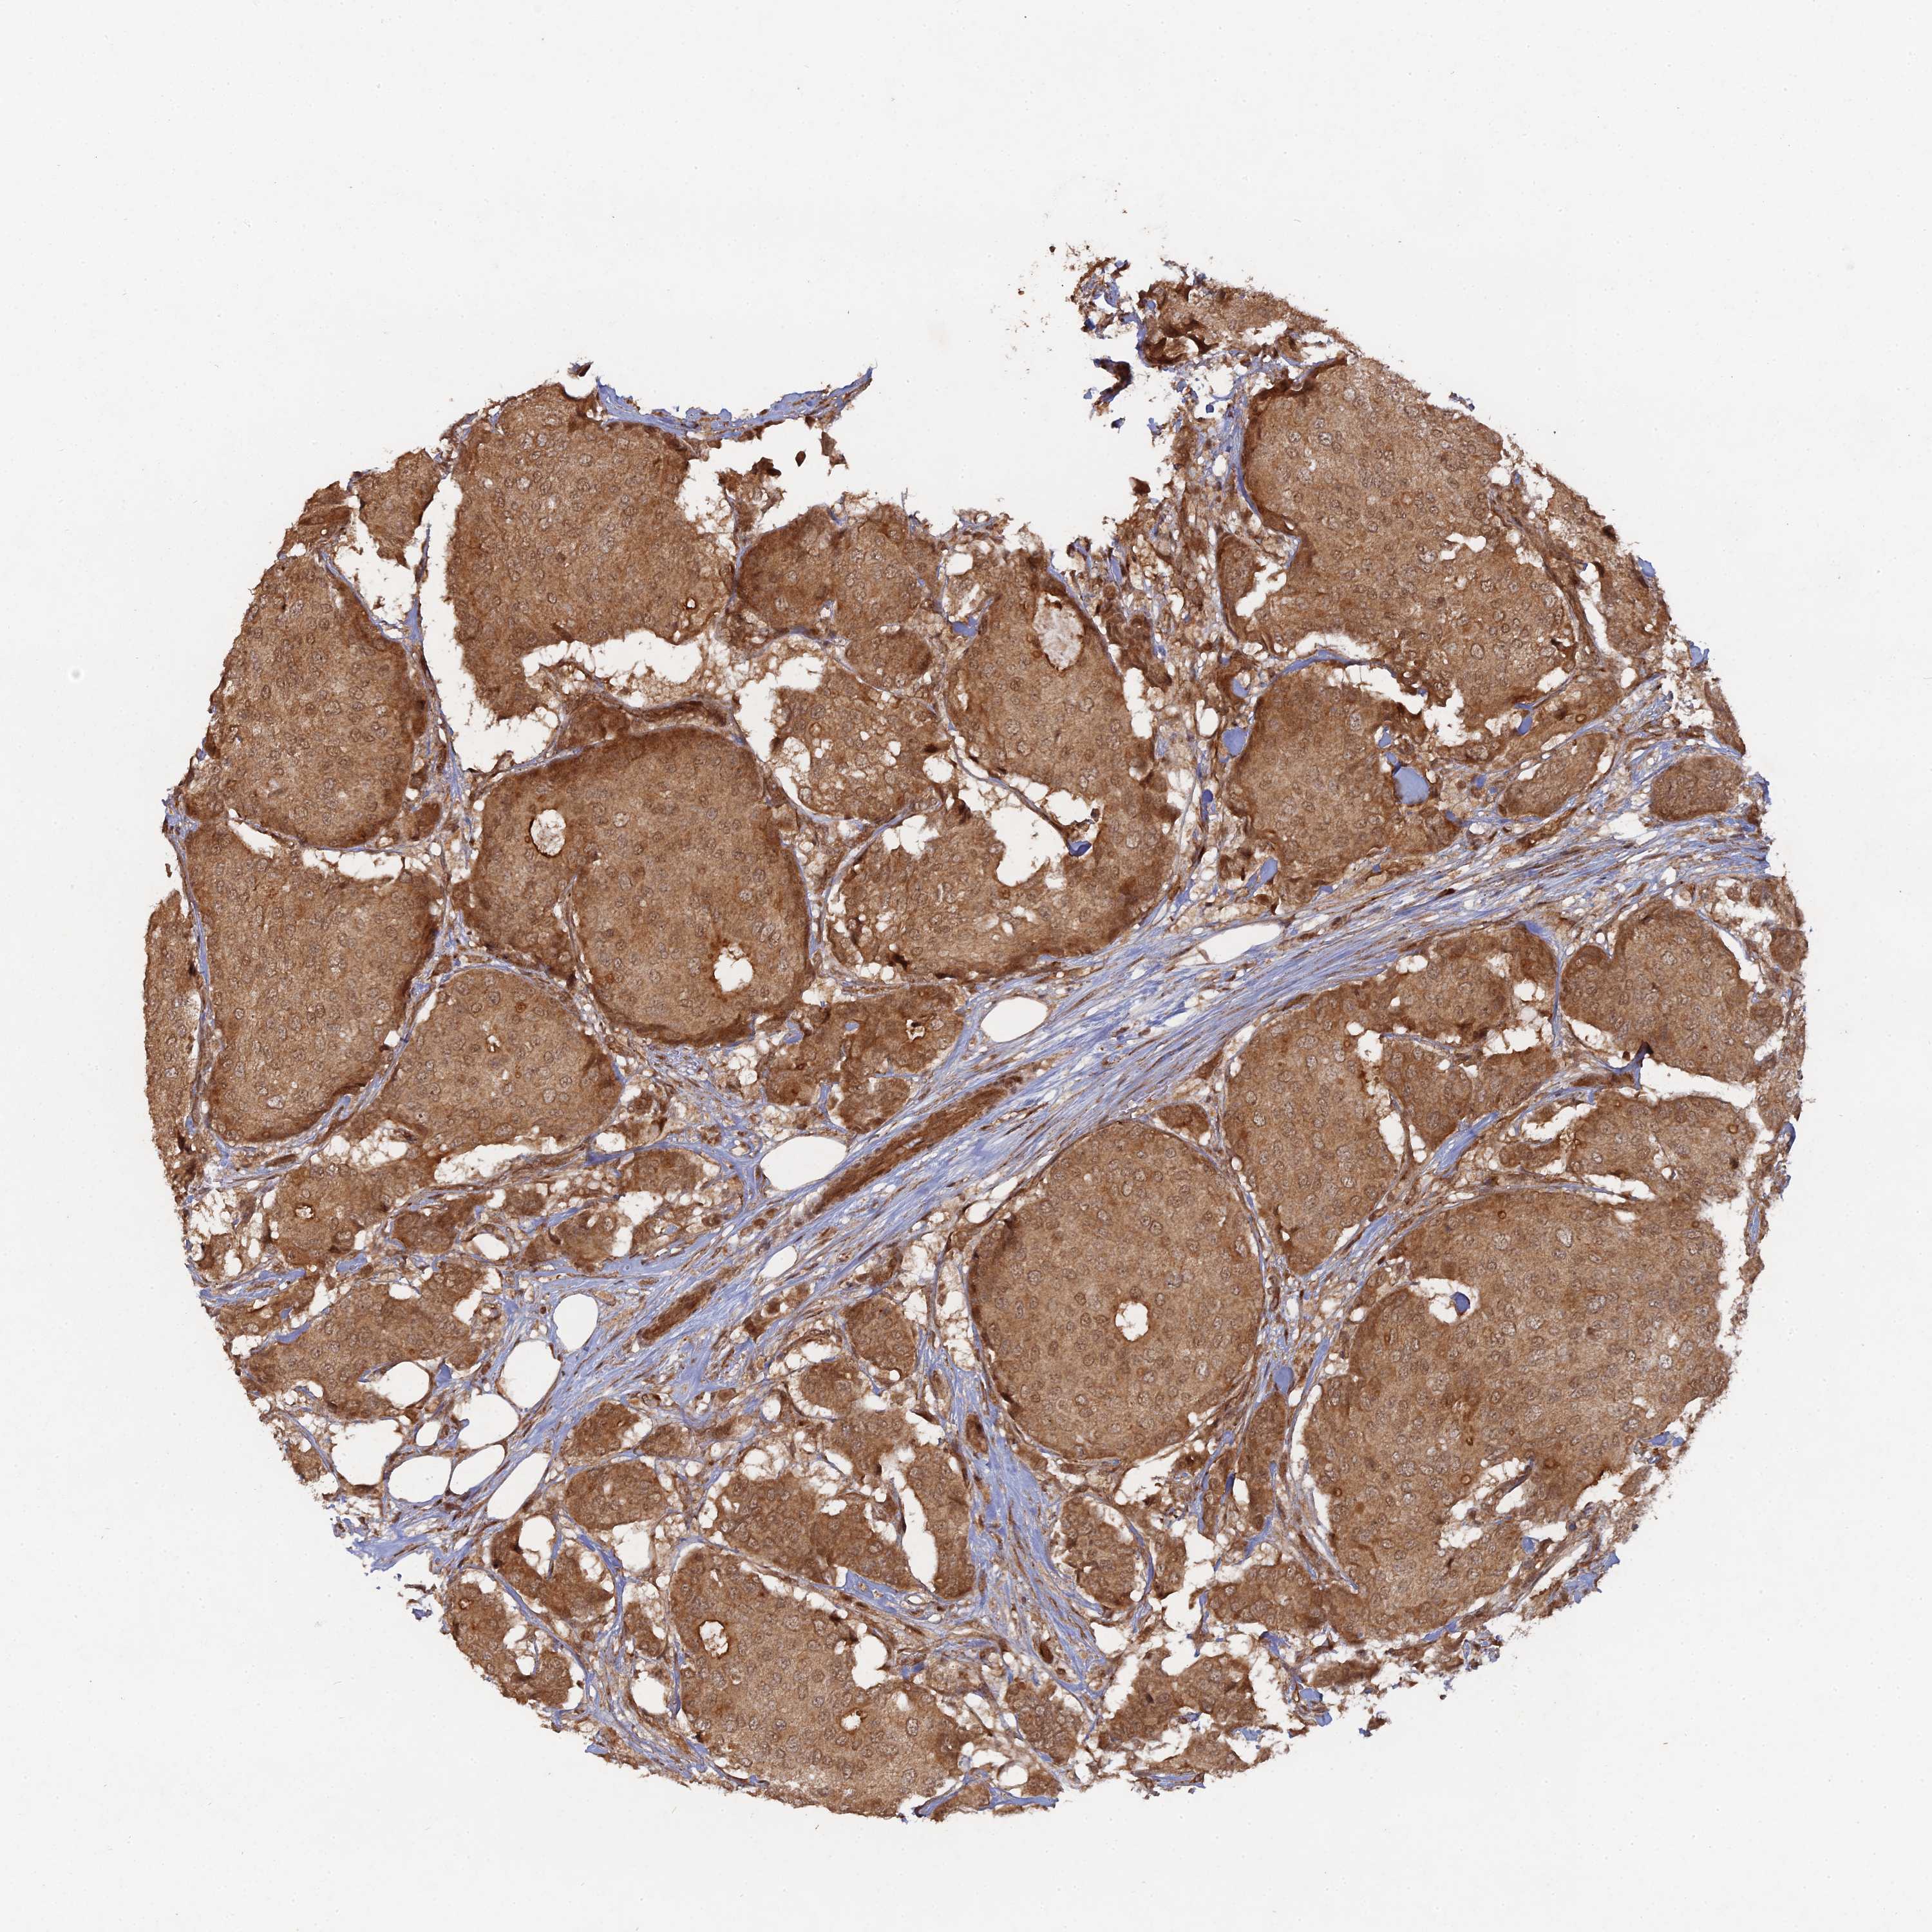

BRCA TCGA BRCA VALIDATION PROTEIN EXPRESSION